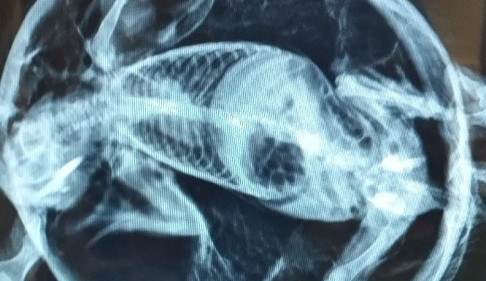

Ježek s balónovým syndromem doputoval do liberecké Archy. Veterináři ho vyfukovali dutou jehlou

Ježků přivítá liberecké záchranné centrum Archa ročně desítky. Letos ale zaznamenalo i jeden velmi neobvyklý případ, dorazil tam totiž ježek s balónovým syndromem. A jak už název napovídá, byl chudák nafouklý jako míč.

Ježek do Archy doputoval v říjnu. „Jednalo se o následek zranění, kdy do podkoží proniká vzduch. Tento úkaz má i svůj název: balónový syndrom. Bez pomoci by samozřejmě uhynul,“ uvádí Archa.

Co s tím? „Veterináři ježka opakovaně doslova vyfukovali pomocí silné duté jehly, aplikovali antibiotika a léky proti bolesti. Během týdne se jeho stav podařilo stabilizovat, i když následná léčba ještě nějakou dobu trvala (měl zraněnou i hlavu a oči). Nyní je Balón stále v péči Archy – už je zazimovaný a hibernuje. Pobude u nás do jara, kdy ho ve vhodnou dobu vypustíme do přírody,“ dodala záchranná stanice.